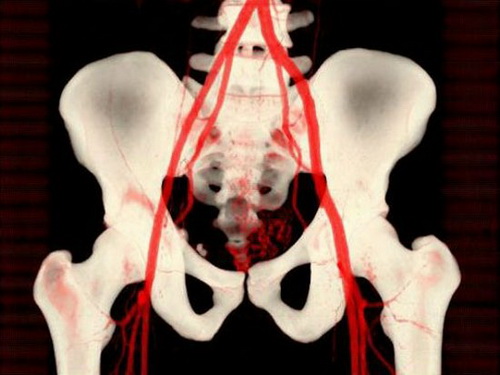

4、CT血管成像

对于此处用以显现骨盆的CT血管成像来说,成像剂会注射到静脉,使血管同软组织形成鲜明对比。电脑软件可以进一步凸显骨骼和血管之间的差别,让医生可以做出更明确、更快速地诊断。